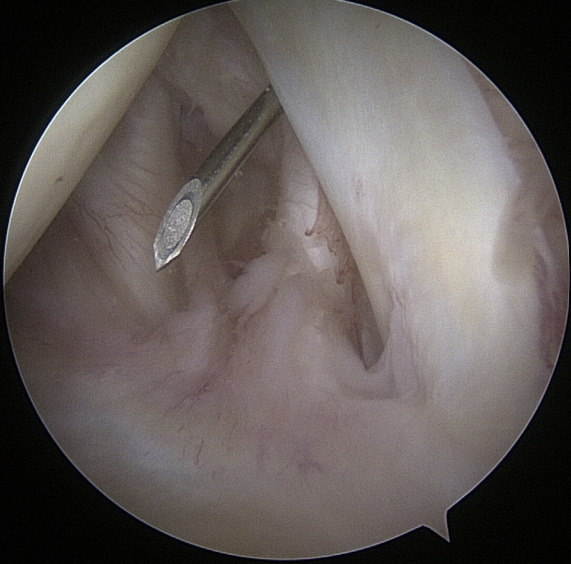

Arthroscopic shoulder surgeries are among the most common minimally invasive procedures (MIS) used to restore shoulder function. Shoulder arthroscopy and arthroscopic rotator cuff repair rates, broken down by geographic location, ranged from 64.96 to 623.6 per 100,000 persons in more recent research.23 The most frequent orthopedic operation for partial meniscectomy is knee arthroscopy, followed by shoulder arthroscopy. Shoulder arthroscopy is a common method for treating pathologic shoulder conditions including adhesive capelusitis, subacromial impingement, illnesses affecting the proximal biceps, rotator cuff tears, labral tears, loose bodies, and degenerative arthritis. Management of shoulder instability and rotator cuff pathology are the two most prevalent reasons for arthroscopic shoulder surgery. There are many advantages of arthroscopy over open surgery. Some of them include a better ability to see intra-articular disease, less complications, shorter recovery times, and less time away from work.6

Joint surgery needed large incisions and arthrotomies to expose and treat joint pathology before arthroscopy and its specialized equipment were widely used in clinical settings. Comparing arthroscopy to such lengthy open arthrotomies, there are a number of benefits. In contrast to MIS arthroscopic treatments, the longer joint exposure results in increased discomfort and recovery time, as well as an increased risk of consequences like infection and arthrofibrosis. Compared to traditional procedures, MIS operations typically cause less discomfort and swelling after surgery. Patients who have arthroscopic treatment so typically recover more quickly, start their rehabilitation earlier, and are able to resume regular activities and employment sooner.22,23

3. Surgical Technique

Instrumentation

When it comes to shoulder arthroscopy, the most common arthroscope utilized is the 4.0 mm 30 scope. A 30-magnification scope is sufficient for most situations. An arthroscopic-assisted coracoclavicular reconstruction, subscapularis repairs, Remplissage procedures, glenohumeral ligament lesions, and humeral avulsion can all benefit from the use of a 4.0-mm 70 arthroscope, which should always be on hand. There should be a large selection of cannulas accessible, and they will differ according on the operation being carried out.25

As the principal penetrating instruments, 5.5-mm blunt-tipped cannulas are often used for portal insertion. Blunt tips are preferred to reduce the likelihood of iatrogenic harm, especially to articular cartilage. Because they are easily passable by the majority of arthroscopy passing devices, 8.25-mm cannulas are often employed for “instrumentation” portals. In addition, cannulas of 6.5 mm or less are commonly used in suture management. Cannulas that are threaded or have locking mechanisms are preferable since they are less likely to come free from the joint. In most cases, one of two methods can be employed: gravity or a pump system. Sufficient management of pressures, usually approximately 60 mm Hg, is necessary to avoid significant soft-tissue edema, which can complicate the use of cannulas and instruments.25